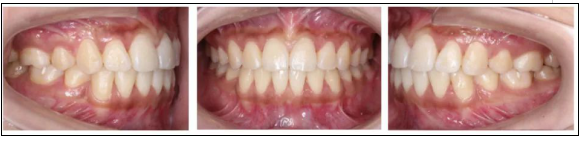

矯正后

上下牙列齊,前牙覆牙合覆蓋正常,中線正,雙側(cè)尖牙及磨牙關(guān)系中性,雙側(cè)后牙尖窩關(guān)系良好。